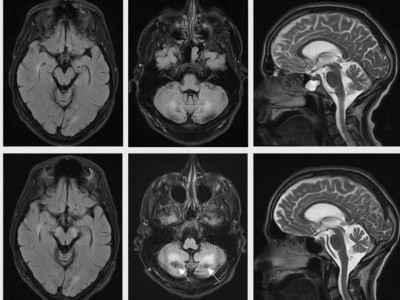

Junger Patient mit zentralnervöser Symptomatik, beidseitigem Katarakt und Durchfall

Ein 30-jähriger Patient entwickelt innerhalb von drei Jahren einen kognitiven Abbau, eine ausgeprägte Sprachstörung und eine schwere Gangstörung. Besonders auffällig sind der beidseitige Katarakt und die wiederholten Durchfälle, die auf eine genetische Erkrankung hinweisen. Kennen Sie die Diagnose?